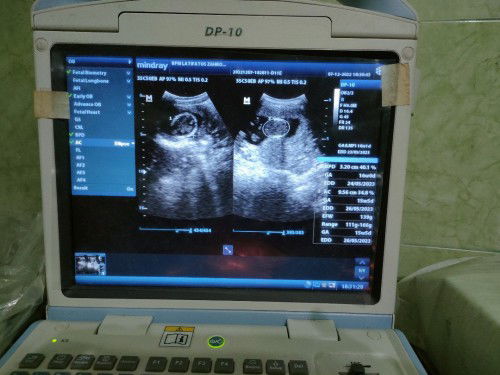

GA (usia kehamilan), BPD (diameter kepala janin), EDD (hari perkiraan lahir), AC (lingkar perut), EFW (berat janin). Kira-kira gitu bund saya pernah dijelasin sama dokter saya. Sebaiknya lain kali kalo periksa ditanyakan sama dokter nya bun kalo blm jelas π. Semangat bun πͺπ»

16weeks, hpl 24/5/2023, panjang janin 9,56, bb 139g.